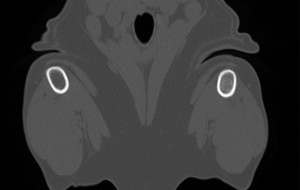

For those of you interested in CT and MRI, we have another great case from the CT/MRI society. This is a 2 year old mixed bree dog who presented for a two week history of progressive neurologic signs including ataxia and circling to the left. Enjoy the case! Access full case and all … [Read more...]